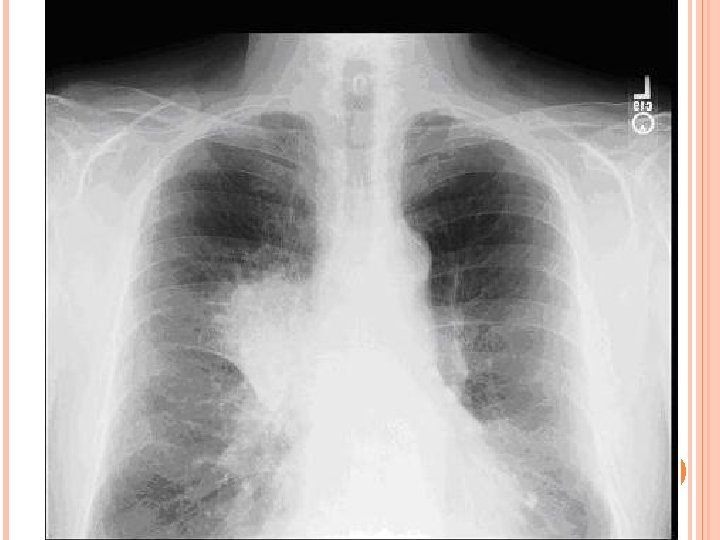

ASPECTE RADIOLOGICE Radiologic se traduce ca o opacitate rotundă sau ovală, de dimensiuni mici omogenă cu contururi netede, intensitate mică cu sediul în parenchimul pulmonar, fără legatură aparentă cu hilul. Uneori se întilneşte o usoară «ombelicare» a conturului care devine bi- sau poli- arcuat.

În evoluţia ulterioară, odată cu creşterea dimensională, opacitatea pierde netitatea şi regularitatea contururilor, datorită infiltrării ţesuturilor învecinate pe calea spaţiilor limfatice; la nivelul hilului devine aparentă adenopatia tumorală.

UTILITATEA INVESTIGAŢIILOR PARACLINICE ÎN CBP PRECOCE Înainte de abordarea investigaţiilor paraclinice utile diagnosticului CBP precoce as vrea să menţionez faptul că acest CBP precoce (tocmai datorită stadiilor iniţiale) poate fi împărţit în: - CBP precoce central: 99 cazuri (75, 6%); - CBP precoce periferic: 32 cazuri (24, 4%). Dacă etiologia si simptomatologia CBP precoce au fost tratate per ansamblu, neexistând diferenţe majore, la investigaţiile paraclinice se utilizează frecvent această împărţire datorită abordului diagnostic diferit în cele 2 situaţii. Radiografia pulmonară a reprezentat primul pas în diagnosticul CBP precoce în judeţul Constanţa, fiind o investigaţie screening. Ea a arătat modificări la 97% din pacienţii cu CBP precoce, modificări care integrate contextului clinic au pus semne de întrebare si au determinat investigaţii suplimentare. “Aceste aspecte radiologice au fost dependente de localizarea centrală sau periferică a tumorii, de prezenţa obstrucţiei bronsice sau a infecţiei. Din analiza bolnavilor studiaţi putem concluziona că CBP precoce a fost predominant central (75% în lotul nostru faţă de 80% în literatură (26, 27)), localizat pe dreapta (60%, identic cu cel din literatură), localizat la nivelul lobilor superiori (60%, de asemenea identic cu cel din literatură (26, 27)). ”